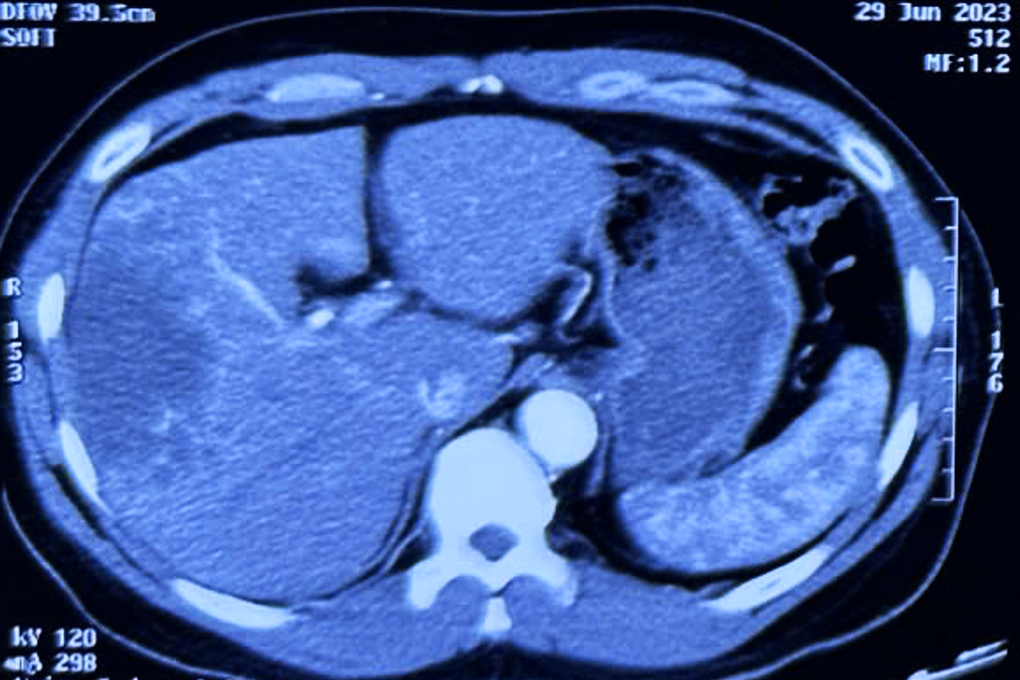

Theo báo cáo trên, ung thư đường mật là loại ung thư hiếm gặp, chiếm 3% các ca mắc ung thư đường tiêu hóa, với tỷ lệ mắc trên thế giới là 0,5-3/100.000 dân/năm. Tại Việt Nam, tỷ suất mới mắc bệnh là 0,1/100.000 dân.

Đáng chú ý, bệnh nhân mắc ung thư đường mật tại chỗ tiến triển hoặc di căn phải đối mặt với tiên lượng kém, với tỷ lệ sống sót 5 năm dưới 5%. Khoảng 80% bệnh nhân khi phát hiện đã được chẩn đoán ở giai đoạn bệnh tiến xa và quá chỉ định phẫu thuật.